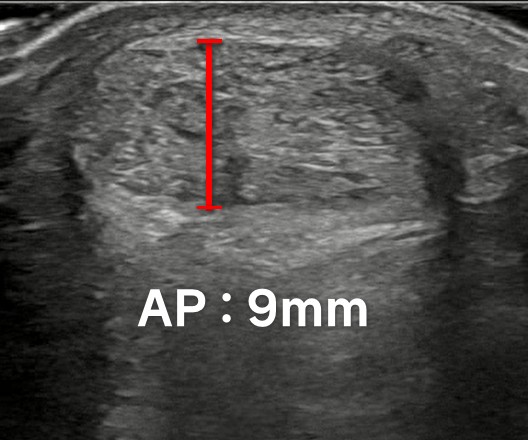

일반적으로 한국인의 아킬레스건은

5mm를 넘지 않는데요.

이 환자분은9mm 정도가 나옵니다.2배 가까이부은 상태죠?

오랜 기간동안

만성 염증에 시달렸던 것을

알 수 있습니다.